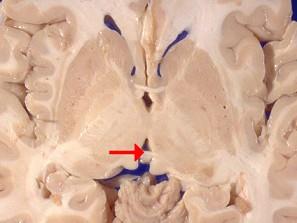

如图箭头所示为大脑哪个部位 ( )A、乳头体B、垂体C、后连合D、室间孔E、前连合

问题 如图箭头所示为大脑哪个部位 ( )

选项 A、乳头体 B、垂体 C、后连合 D、室间孔 E、前连合

答案 C